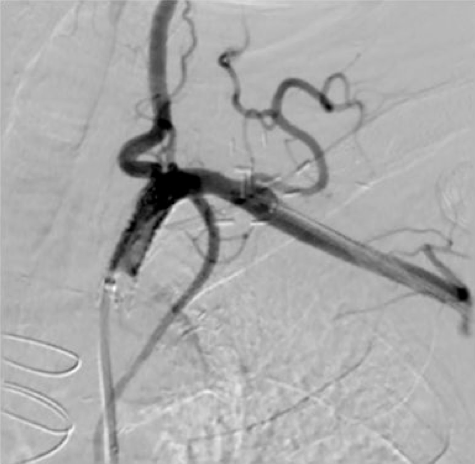

Figure 2. Computerized tomography angiogram taken upon admission to our facility. Bilateral SCA-CCA graft occlusion can be noted (white arrows), along with the surgically ligated right SCA (black arrow) (click thumbnail to view larger image).

Upon transfer to our facility, a computed tomography angiogram (CTA) was performed, which revealed the bilaterally occluded bypass grafts and the ligated right SCA (Figure 2). Cardiac catheterization and angiography showed that both the proximal RCA and the left main were occluded. The SVG to RCA and OM1 were patent; SVG to D1 was occluded. The bilateral subclavian steals could be visualized with contrast injection into the bracheocephalic and left common carotid arteries (Figures 3 and 4). The LIMA was faintly visualized during the late filling phase of the left carotid angiogram (Figure 4); the left SCA and LIMA filled via collaterals from the left vertebral artery.